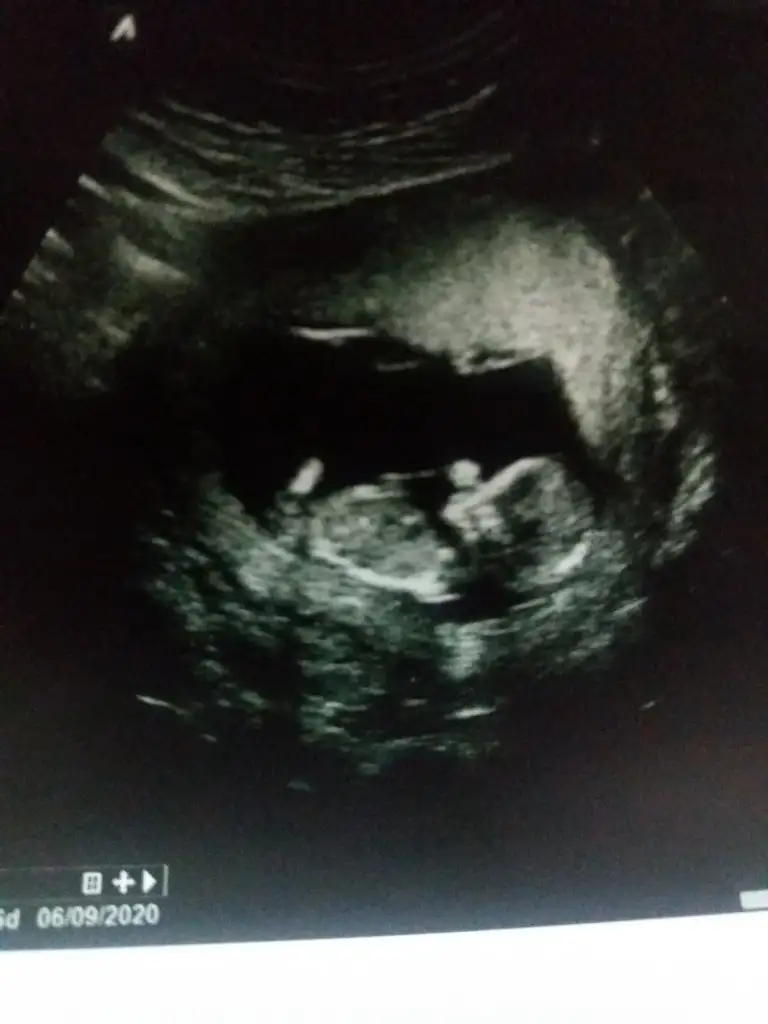

iyi akşamlar kızlar bizede bir tahmin Varmı 12+6 haftalığız burada

• 1583005815531311535667.webp

1583005815531311535667.webp

25,8 KB · Görüntüleme: 44